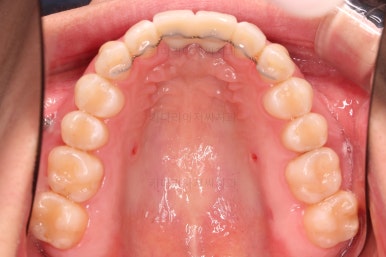

1. 초진

부산개방교합 키다리아저씨치과에 처음 내원 시 입안의 모습입니다.

전반적으로 치열이 삐뚤고요.

앞니쪽이 다물어지지 않는 개방교합(오픈바이트, open bite) 을 보였습니다.

어금니 맞물림을 보면 앵글씨 2급 부정교합 양상이어서 위아랫니가 모두 1대1로 부딪히고 있는 상태였습니다.